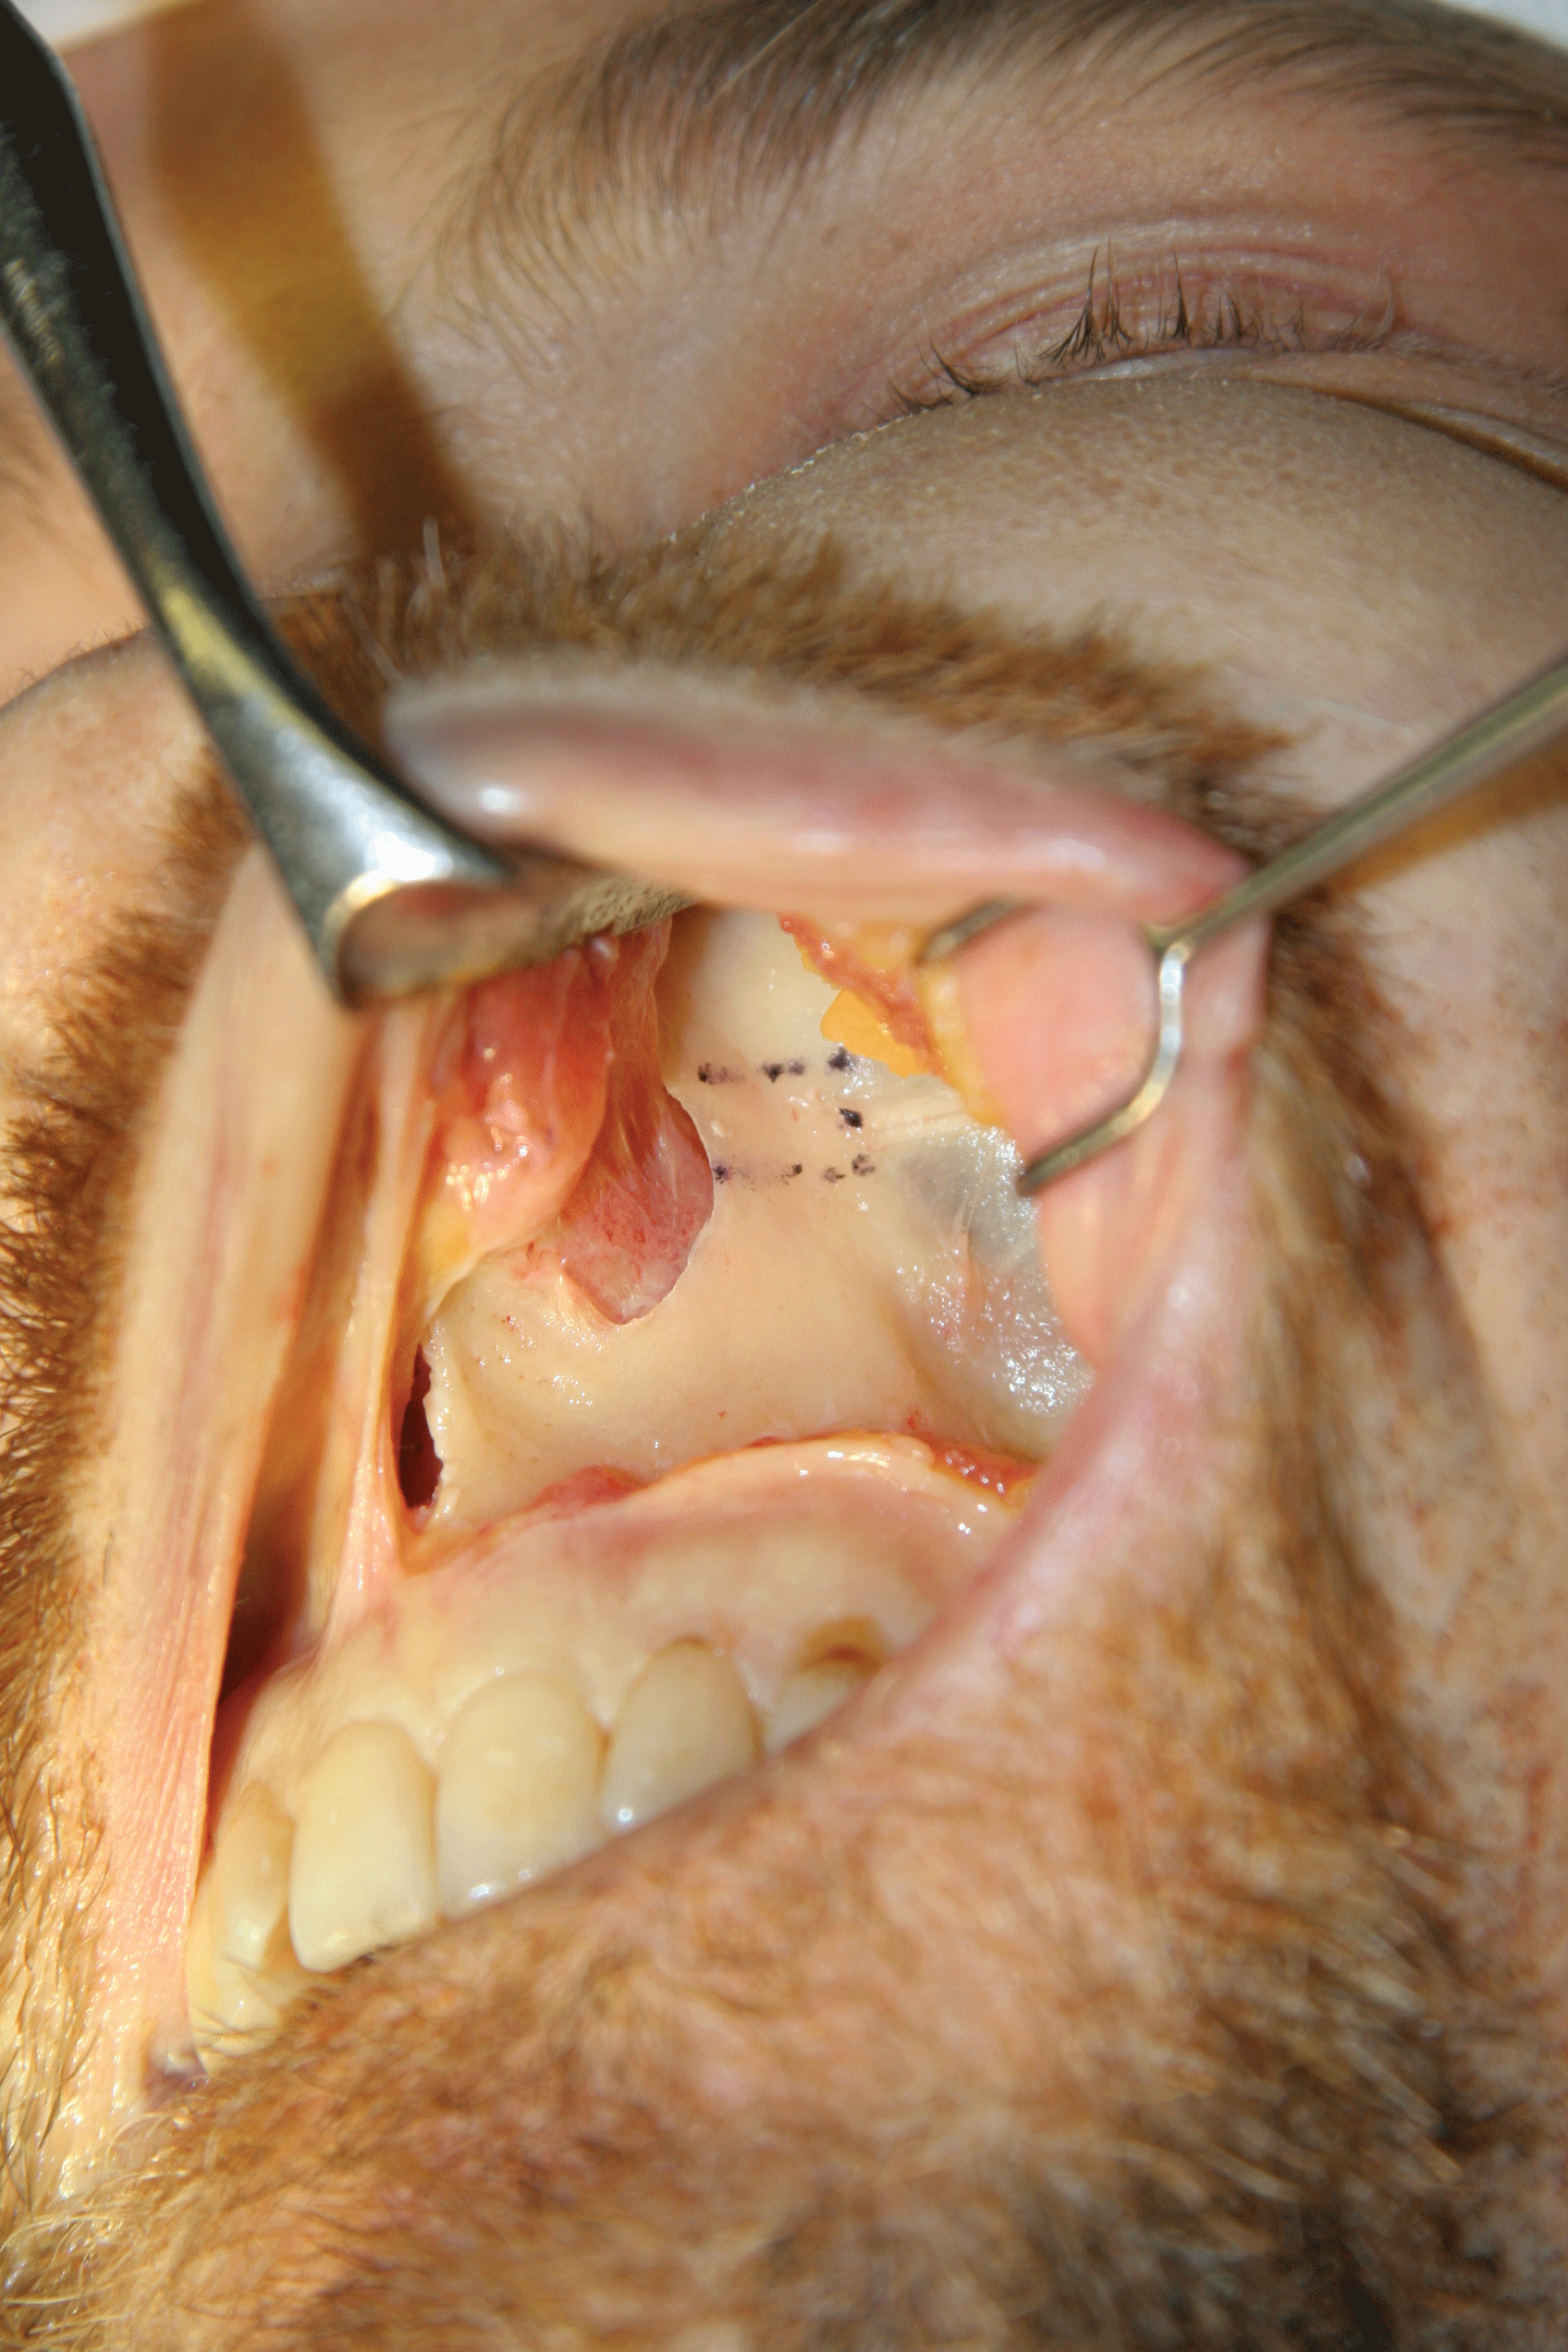

A 52-year-old man presented with chronic left sided nasal obstruction despite prior functional septorhinoplasty and turbinate reduction 3 years earlier. His operative report indicated septal cartilage had been used for intranasal grafting including batten grafts, spreader grafts, and rim grafts. Examination revealed left internal valve stenosis and collapse in the presence of a straight septal remnant, normal inferior turbinates, and normal external nasal valves. He consented to PMA on the affected side using an alloplastic implant as described above (Figure 3). The procedure was well tolerated. He was assessed at 3, 6, 12, and 24-month intervals and felt his problematic airway obstruction had resolved.

.

Figure 3: Intraoperative view of the modified Titan implant, fixated to the left piriform margin.